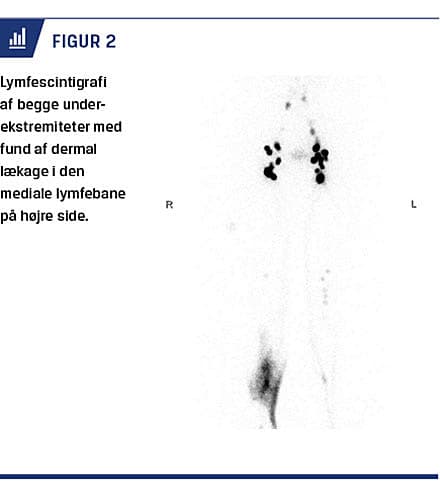

På grund af vedvarende ødem blev patienten et halvt år senere, efter forudgående vurdering på en karkirurgisk afdeling, viderehenvist til Lymfødemklinikken på Bispebjerg Hospital. Diagnosen lymfødem blev her bekræftet ved lymfescintigrafi, som viste dermal lækage på højre crus (Figur 2).